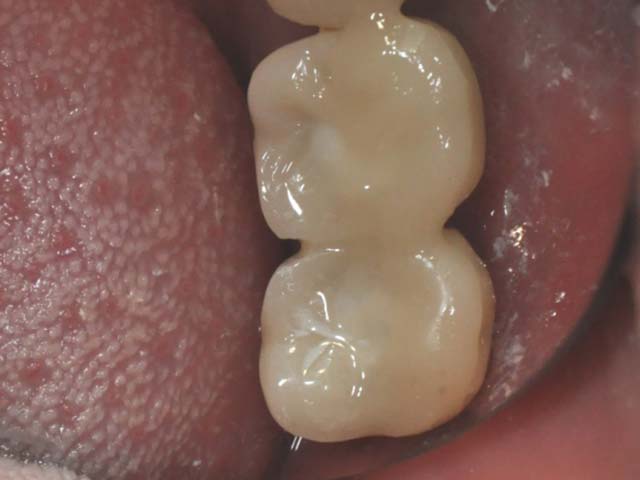

牙橋嚴重蛀牙,即拔即種,避免二次傷口 首頁 案例分享 人工植牙 牙橋嚴重蛀牙,即拔即種,避免二次傷口 多年前製作之牙橋,因為二度齲齒,導致支台齒蛀蝕,而需重新製作 牙橋支臺齒嚴重蛀牙 STEP1.拔除殘根並植入兩根植牙 STEP2.骨粉填補缺損骨頭缺陷 STEP3.三個月後,準備製作正式假牙 STEP4.正式假牙完成